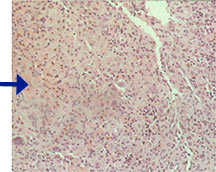

Microscopic Pathology

- Langerhans cell is diagnostic and clonal proliferation

- Nuclei show prominent nuclear groove (coffee-bean)

- Also composed of eosinophils and other inflammatory cells (non diagnostic component)

- Birbeck Granules: Electron Microscopy demonstrates granules that often take the form of a tennis raquet and form from complex invaginations of the cell membrane

- Vimentin, CD1 and S-100 positivity